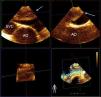

Mid-esophageal orthogonal views of the superior vena cava (SVC), ascending aorta (AO) and right pulmonary artery. Three-dimensional (3D) transesophageal echocardiography shows a large thrombus in the right pulmonary artery (white arrow), extending from the main pulmonary artery bifurcation. 3D reconstruction improves the morphological characterization of the thrombus.

A 40-year-old woman was admitted to the intensive care unit after extensive thoracic burns. During surgical debridement, she experienced rapidly progressive hypoxemia and hypotension requiring high-dose vasopressors, and oxygen saturation remained low despite 100% inspired oxygen concentration. Three-dimensional transesophageal echocardiography was performed, which showed a large thrombus in the right pulmonary artery, extending from the main pulmonary artery bifurcation (Figure 1). It also revealed right ventricular dilatation and severe tricuspid regurgitation (Figure 2A). Given the high bleeding risk associated with recent surgery, a decision was made to perform percutaneous thrombectomy with low-dose intra-arterial fibrinolysis instead of systemic full-dose thrombolysis. Pre-intervention angiography demonstrated a large filling defect in the right pulmonary artery with impaired distal flow (Figure 3A). Abundant thrombotic material was obtained (Figure 3C) and significant improvement in pulmonary circulation was noted (Figure 3B). After the procedure, the patient experienced a dramatic improvement in hemodynamic and respiratory parameters, enabling discontinuation of vasopressors and the use of lower inspired oxygen concentration. Chest radiography demonstrated wedge-shaped pleural based opacities (the “Hampton's hump” sign, Figure 3D). Follow-up echocardiography performed 48 hours later showed resolution of right ventricular dilatation and tricuspid regurgitation (Figure 2B).